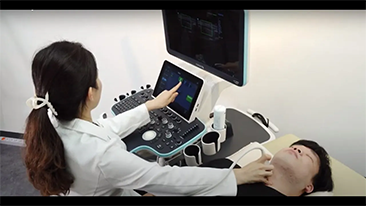

Von der optimalen Kabelf├╝hrung bis zum Gelw?rmer ist an alle wichtigen Features gedacht worden. Das Resona 7 ├╝berzeugt als modulares Sonographiesystem der Extraklasse. Es bew?hrt sich in der Praxis als ein patientenfreundlicher Begleiter, der mit Liebe zum Detail konzipiert worden ist.